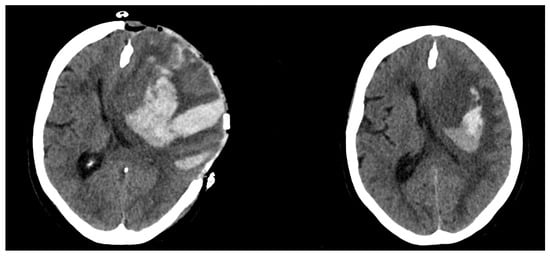

Postoperative Hematoma Expansion in Patients Undergoing Decompressive Hemicraniectomy for Spontaneous Intracerebral Hemorrhage

3.1. Preoperative/Postoperative Size Differences